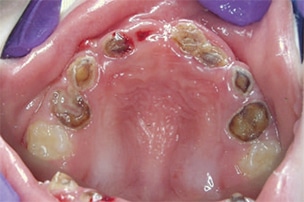

Severe ECC (S-ECC) is defined as any sign of smooth-surface caries in children younger than age 3. Additionally, in children ages 3 through 5, one or more dmf surfaces in primary maxillary anterior teeth, or a dmf score of ≥ 4 (age 3), ≥ 5 (age 4), or ≥ 6 (age 5) surfaces also constitutes S-ECC.3 The typical early sign of ECC is the crescent shaped white spot lesion at the gingival margin (Figure 1 to Figure 4).